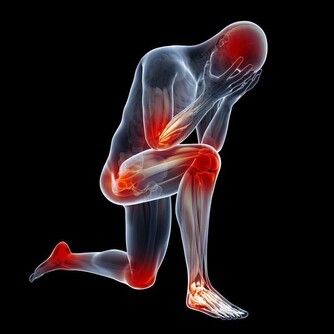

賴床會導致尿液在體內長時間的滯留,於是尿液當中的有毒物質就會損害我們身體的健康。另外,長時間的賴床,會減緩人體的血液循環,導致營養在體內不能很好的傳送,於是肌肉和關節中代謝產生的物質也不能被排除體外。